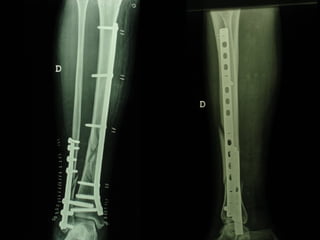

Dal Gennaio 2000 al Febbraio 2006 abbiamo trattato 167 fratture chiuse  con placca percutanea  in 164 pazienti :  27 lesioni diafisarie di gamba, 12 piloni tibiali ,  11 fratture prossimali di tibia, 36 fratture sovracondiloidee di femore, 17 fratture diafisarie di femore, 43 fratture metaepifisarie prossimali di omero, 21 diafisarie d’omero.  156 guarigioni 8 fallimenti

I buoni risultati ottenuti dipendono da 5 punti fondamentali:   una accurata riduzione percutanea della frattura  precise vie di accesso  l’utilizzo della placca che consenta il più lungo braccio di leva possibile il pretensionamento della placca  una sintesi con un ridotto numero di viti

Placche lunghe e pretensionate

Placche lunghe e pretensionate Sintesi con un ridotto numero di viti

Dal Gennaio 2000 al Dicembre 2005 27 placche LISS di femore